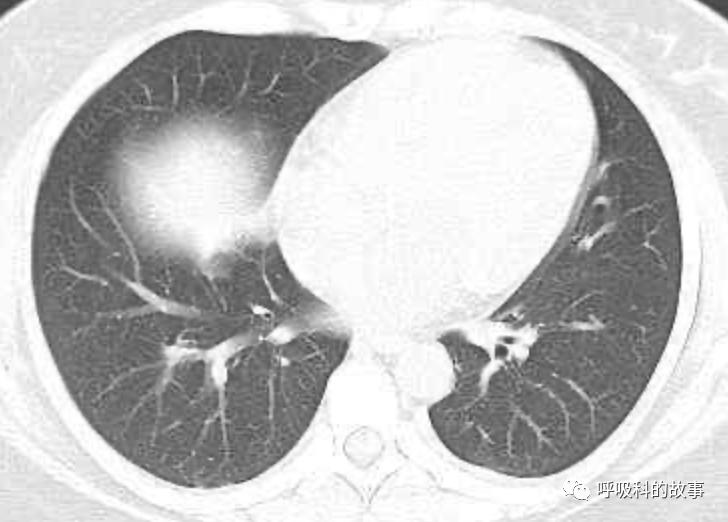

可是在6月26日(往院第18天)仍持续发热的情况下复查肺部CT,肺部病灶已明显吸收了。那么患者发热的原因到底是什么呢?为什么患者高热的情况下血白细胞不升反降,C反应蛋白也没有明显增高?这个时候消化科医生也迷茫了,这可怎么办?于是请感染科和呼吸科医生一起会诊,共商计策。

基于这样的规律,加上没有发现感染部位,我们一致判断患者发热的原因是药物热。由于抗菌素是在发热后使用的,且莫西沙星和头孢类药物很少引起药物热,于是真正的凶手应该是在入院后就使用的硫普罗宁或者丁二磺酸腺苷蛋氨酸,在查阅大量文献后,我们认定就是硫普罗宁引起的药物热。